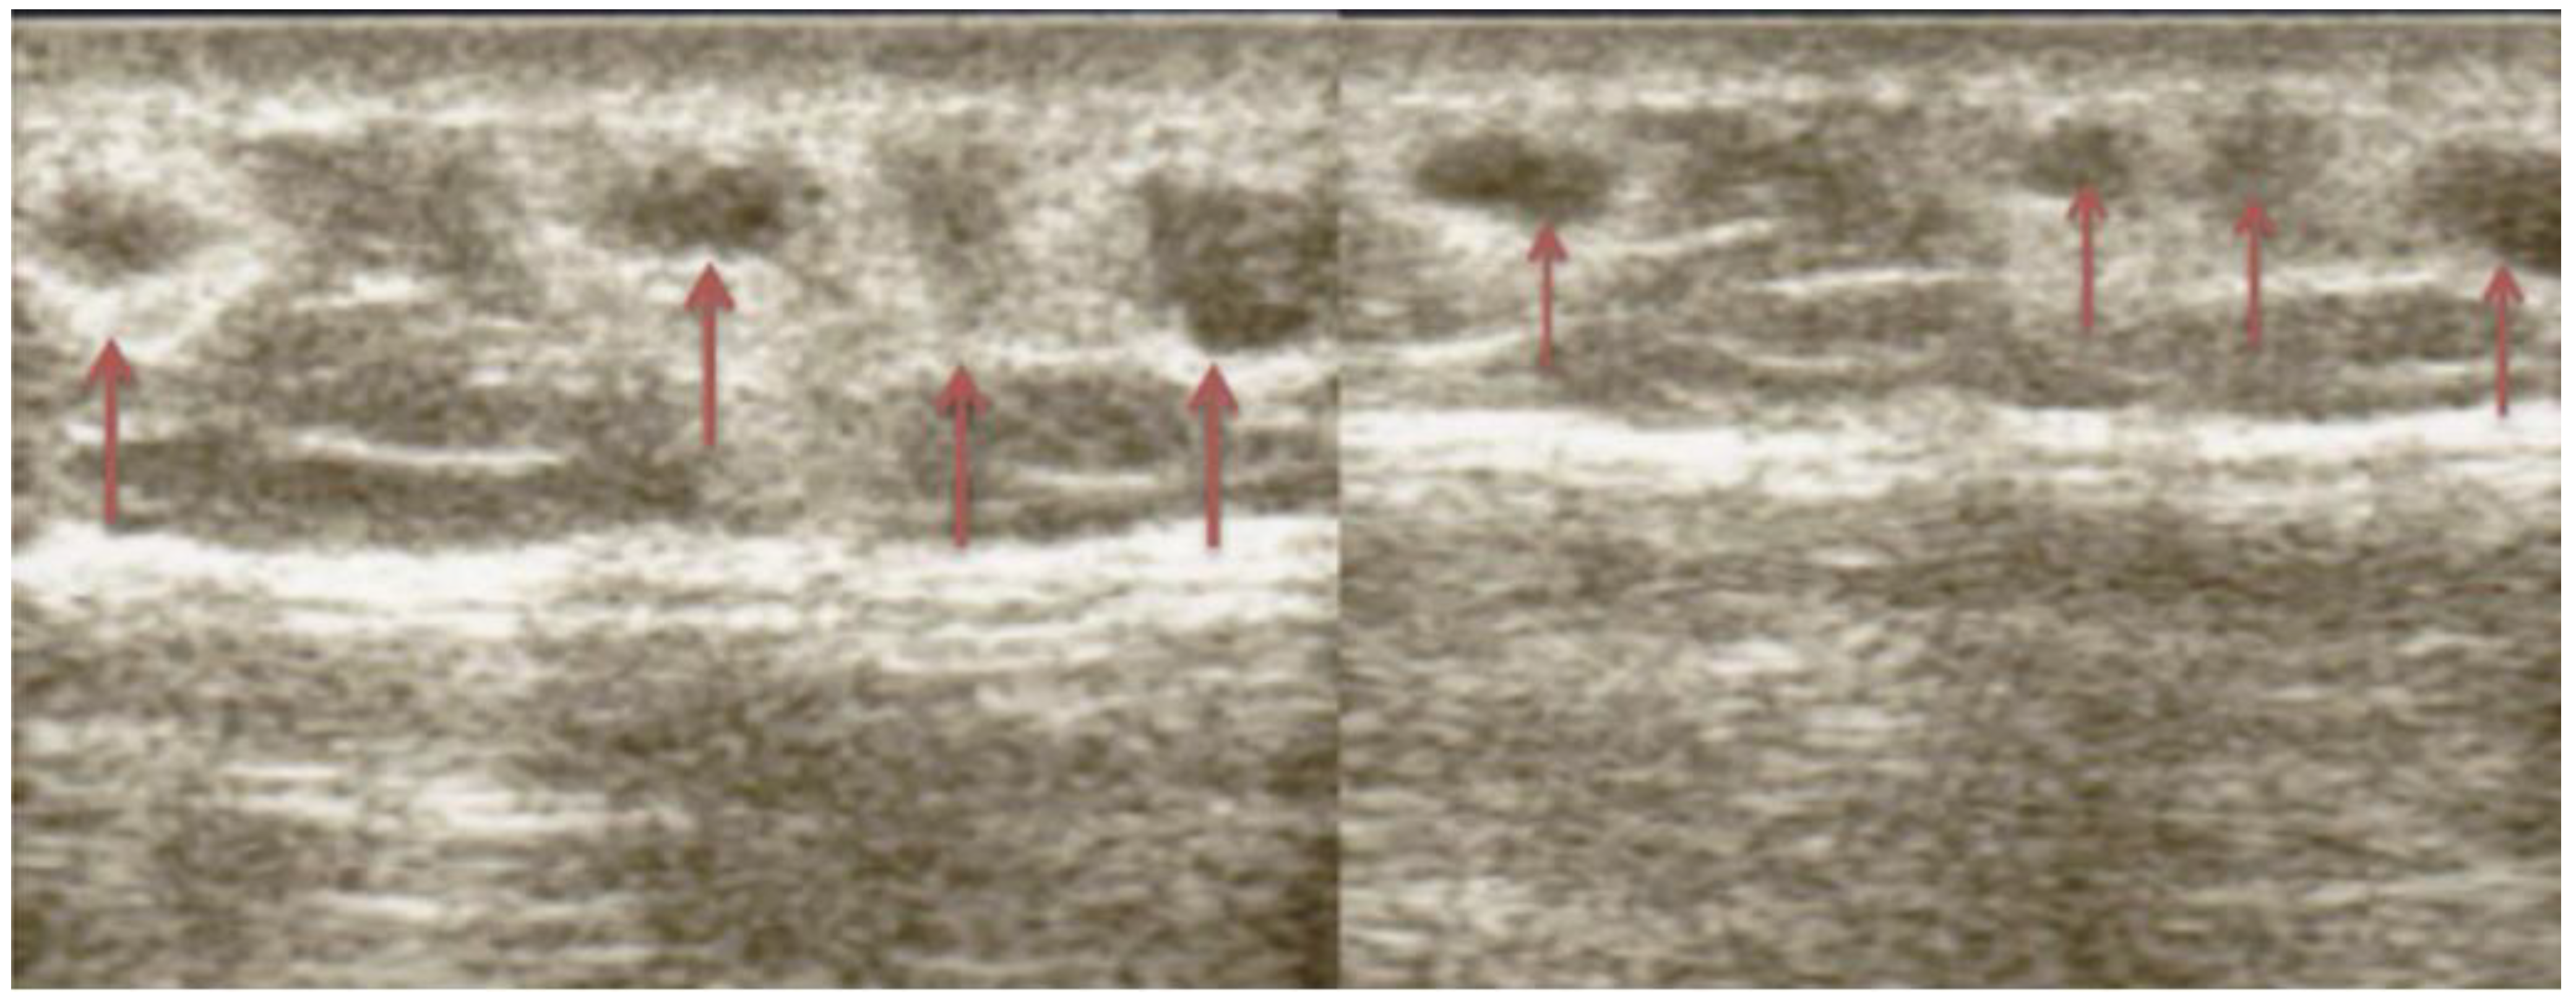

- Kapeluto, J.E.; Paty, B.W.; Chang, S.D.; Meneilly, G.S. Ultrasound detection of insulin-induced lipohypertrophy in Type 1 and Type 2 diabetes. Diabet. Med. 2018, 35, 1383–1390. [Google Scholar] [CrossRef] [PubMed]